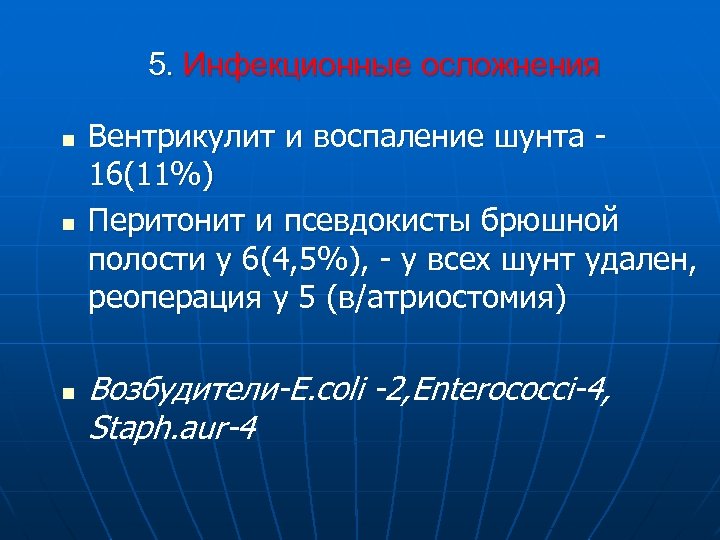

5. Инфекционные осложнения n n n Вентрикулит и воспаление шунта 16(11%) Перитонит и псевдокисты брюшной полости у 6(4, 5%), - у всех шунт удален, реоперация у 5 (в/атриостомия) Возбудители-E. coli -2, Enterococci-4, Staph. aur-4